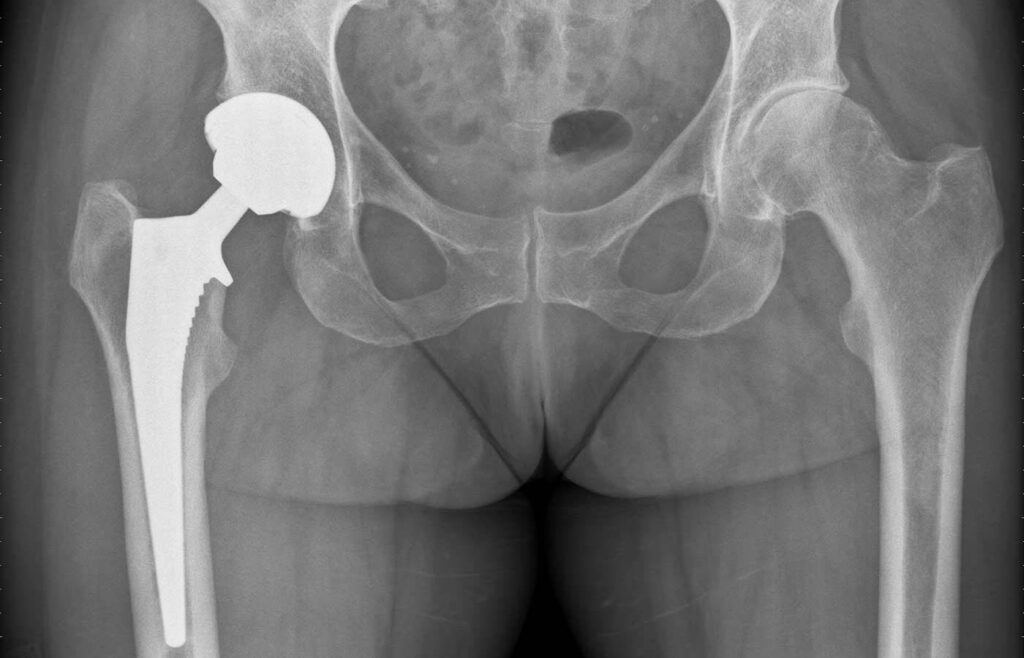

nach Implantation